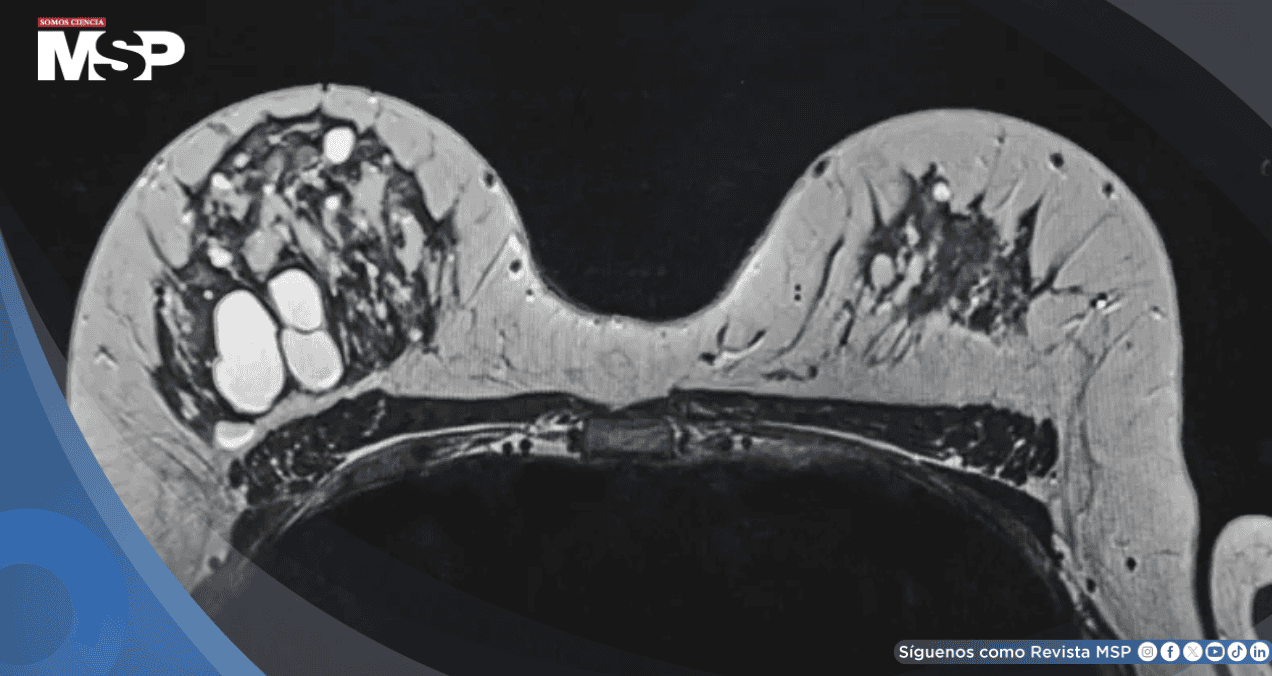

Investigación sugiere que las mujeres con alta densidad mamográfica tienen mayor probabilidad de desarrollar subtipos tumorales agresivos como HER2+ y triple negativo, especialmente en premenopáusicas y mujeres con sobrepeso.

Los resultados indican que las mujeres con mayor proporción de tejido fibroglandular —lo que se conoce como alta densidad mamaria— podrían tener más probabilidades de presentar tumores con peor pronóstico.

La densidad mamográfica media fue del 26 %, pero las mujeres con niveles superiores al 50 % mostraron una distribución más desfavorable: menos tumores HR+ y un aumento del 36 % en tumores HER2+ y del 23 % en triple negativo, respecto a las mujeres con menor densidad mamaria.

La densidad mamográfica es un factor de riesgo reconocido para el cáncer de mama, y podría influir en el desarrollo de subtipos tumorales de manera diferenciada.